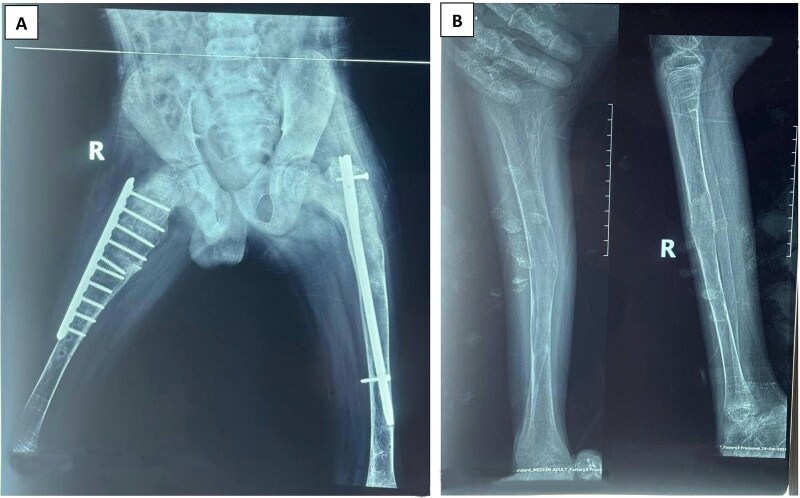

McCune-Albright syndrome (MAS) is somatic mosaicism disorder due to mutations in GNAS gene leading to a combination of fibrous dysplasia of bone, café-au-lait skin lesion and hyperfunctioning endocrinopathies. We report an 11-year-old boy who presented with bone pains and easy fractures with minor traumas that were treated with surgeries. He had multiple café-au-lait lesions, hypertrophic scars of prior surgeries and deformities of bones on examination and primary hyperthyroidism on investigation. His condition was initially misdiagnosed as osteogenesis imperfecta but the finding of hyperthyroidism reaffirms the diagnosis of MAS. He was treated with pamidronate, carbimazole and surgical operations to correct bony deformities.